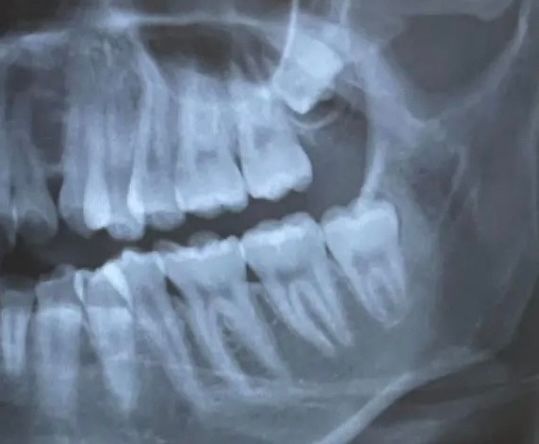

晚上打扰各位大神了~ 因为之前去洗牙时,医师有提到我的左右两边的智齿都应该要拔掉 自从上次在那间拔完右边,就对那间牙医印象极差…(各方各面,信任度大降) 肿了一个多礼拜後,至今恐惧都还在orz (人生中第一次清创也是献给他们了…) 有点怕之後智齿没有清洁好,蛀牙会更难处理 目前剩左下那颗,如果长这样是不是要去找比较专业的口外医师拔? https://i.mopix.cc/Blixje.jpg

5F:推 sunsonsam: 绝对要拔 而且看起来也没有到很难处理 02/13 22:06